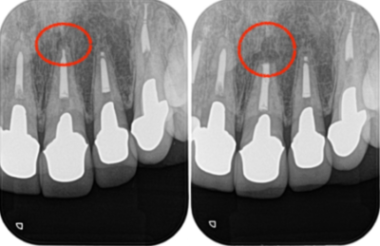

当院にて詳しく診査を行ったところ、左上1番の歯に根尖性歯周炎(虫歯や歯髄炎が進行し、歯の根の先周辺の歯周組織に炎症が生じた状態)が確認されました。

この炎症が、患者様が感じていた違和感の主な原因であると診断しました。

レントゲン画像がこちらになります。